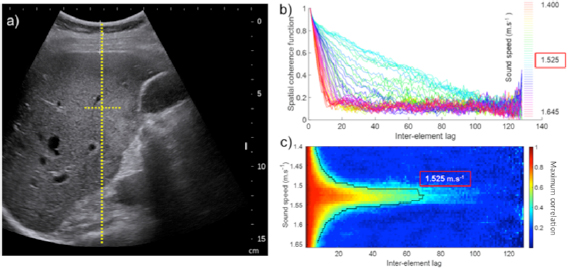

The estimation of the acoustic sound speed in the liver is based on the estimation of the spatial coherence function of backscattered RF signals coming from a chosen focal region. As there is no focus performed in transmit, the focusing process is performed by a synthetic summation of backscattered signals coming from different tilted plane waves transmission. This consists of a virtual transmit focusing using coherent compounding of Hadamard transmitted signals. This virtual transmit focusing is performed using time delay laws for different choices of acoustic sound speeds ranging from 1450 m s−1 (pure fat) to 1650 m s−1. Because the scatterers in the focal spot are a random distribution of scatterers that are much smaller than the wavelength (Rayleigh Scatterers), the spatial coherence function of the backscattered signals is a triangle function in application of the Van Cittert Zernike theorem (Mallart and Fink 1994). The area under the curve becomes maximal when the acoustic sound speed chosen for the beamforming process corresponds to the acoustic sound speed of the medium (see figure 2).

Figure 2. Description of the post processing method based on iterative adaptive focusing and acoustic SSE. (a) estimation and correction of average acoustic sound speed by optimizing the spatial coherence of backscattered echoes independently for multiple focuses, (b) steering of received focus beams towards a single spot, (c) virtual point source generation using rephasing and coherent summation of signals, (d) aberration correction using adapted time delays.

Conventional US was first performed to position the abdominal curved probe (SC6-1) driven by an ultrafast scanner (Aixplorer®, Supersonic Imagine, France) in the right subcostal view and to ensure that the hepatic capsule was parallel to the US probe. The SSE ultrasonic sequence was then performed while avoiding the presence of large hepatic vessels or large US artifacts in the image (figure 3(a)). The 2 s ultrasound acquisition sequence was then performed during neutral respiratory apnea. The focal spot used to estimate the spatial coherence function was located at 60 mm depth, at the focal elevation depth of the SC6-1 probe. The spatial coherence function of backscattered signals coming from the focal spot was calculated for different values of the liver acoustic sound speed (figures 3(b) and (c)). The optimal sound speed corresponding to the maximal area under the curve of the spatial coherence function was then selected to perform the adaptive focusing procedure. The ultrasonic fat fraction was then deduced from the theoretical equation (7).

Figure 3. Example of in vivo acquisitions on a single patient: (a) ultrasound B mode image and focal spot located at the elevation focal depth z = 60 mm used for virtual transmit focusing, (b) spatial coherence function of backscattered signals from the focal spot estimated using different average sound speeds during the beamforming process of raw ultrasonic data. This shows the triangle shape of the coherence function at the optimal sound speed, (c) same as (b), in a 2D colormap representation highlighting the largest triangle shape obtained for the optimal selection of sound speed as predicted by the Van Cittert Zernike theorem. The blue curve is one ISO-value, i.e. a curve of constant maximum correlation value (0.3) for each sound speed. The sound speed characterizing the medium ensures the highest lag for a given maximum correlation.